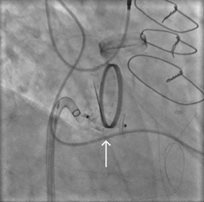

Under general anesthesia and with transesophageal echocardiography guidance, the defect is successfully crossed using a hydrophilic guidewire introduced via the right radial artery. A 6-French guide catheter is advanced across the defect, and a 12-mm nitinol vascular plug is deployed. Prior to device release, selective coronary angiography of the left main coronary artery is performed to confirm vessel patency (see Fig. 3).

Fig. 3. Transcatheter paravalvular leak closure. The orange arrow identifies the distal aspect of the vascular plug, positioned below the aortic valve. The white arrow identifies the proximal aspect of the plug, in the left coronary cusp of the aortic root and outside of the prosthetic aortic valve frame. Coronary angiography reveals a patent left main coronary artery.

Post-deployment TEE demonstrates complete elimination of the paravalvular leak.